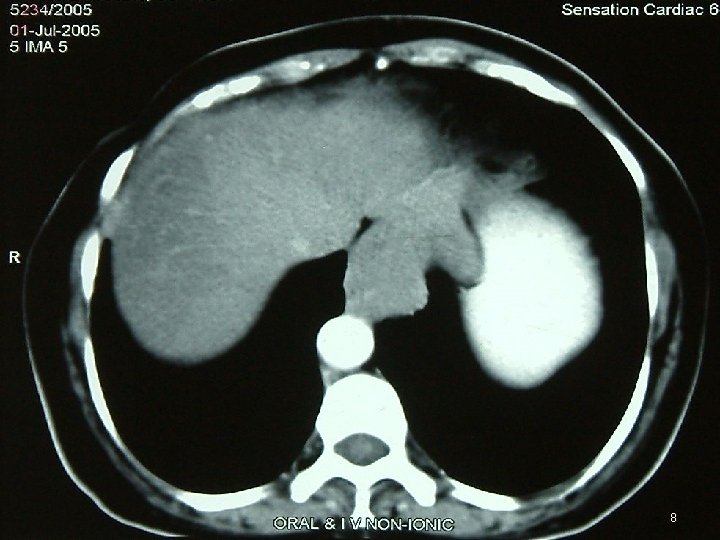

Investigations • • • Chest X Ray USG CECT EUS Ba Swallow 3

4

5

6

7

8

Diagnosis • FDG PET = mandatory ►FDG-PET CT scan is ideal • MD-CE-CT = image modality of choice for abdomen (if FDG-PET-CT is not available) • MR • Evaluate by Chol or RECIST criterion 46